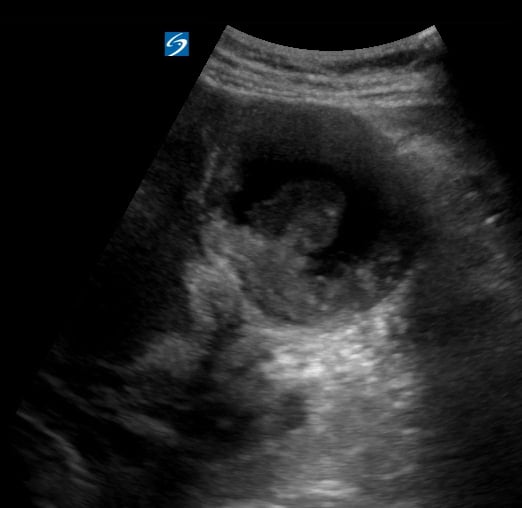

Ultrasound is the primary imaging modality for diagnosing and characterizing uterine fibroids due to its non-invasiveness and real-time capabilities. Sonography allows for the visualization of fibroid size, location (e.g., submucosal, intramural, subserosal), and internal features, aiding in treatment planning. Understanding fibroid characteristics via ultrasound is crucial for effective patient management in women’s health.